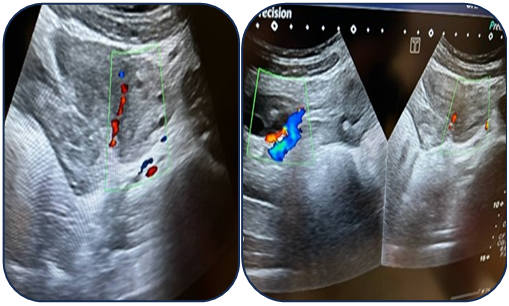

Case 1: A 17-year-old female presented with acute pain. Ultrasound revealed a 95 mm complex left ovarian cyst with no Doppler flow (Fig. 1). Emergency laparoscopy confirmed a 720-degree torsion. Detorsion and cystectomy were performed. Intraoperative findings are shown in Fig. 2, Fig. 3, and Fig. 4. Histopathology reported a serous cystadenoma. Postoperative ultrasound on day 5 confirmed a viable ovary (Fig. 5). | Figure 1. Ultrasound findings of a left ovarian cyst with torsion |

| Figure 2. Intraoperative laparoscopic view 1 |

| Figure 3. Intraoperative laparoscopic view 2 |

| Figure 4. Intraoperative laparoscopic view 3 |

Case 2: An 11-year-old female presented with a torsed, edematous left ovary (69x49 mm) on ultrasound (Fig. 6). Laparoscopic detorsion alone was performed (Fig. 7 & Fig. 8). Serial postoperative ultrasounds documented the gradual resolution of edema and the return of vascularity by day 20 (Fig. 9), confirming ovarian recovery. | Figure 6. Preoperative ultrasound examination of the left ovary |

| Figure 7. Intraoperative laparoscopic view during detorsion 1 |

| Figure 8. Intraoperative laparoscopic view during detorsion 2 |